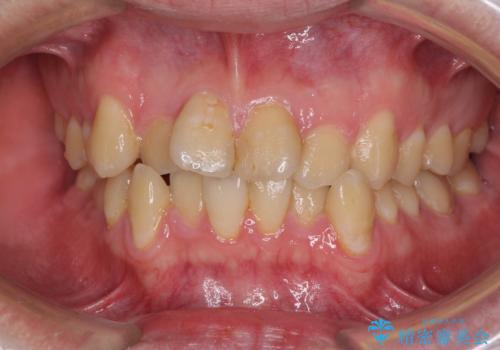

- 上下のデコボコと前歯のクロスバイトを改善したいとのことで来院された患者様です。

マウスピース矯正での自己管理には自信がないとのことで、ワイヤー装置による矯正治療を行うこととしました。

デコボコの程度は強かったのですが、口元の突出感はなかったため、非抜歯矯正としました。